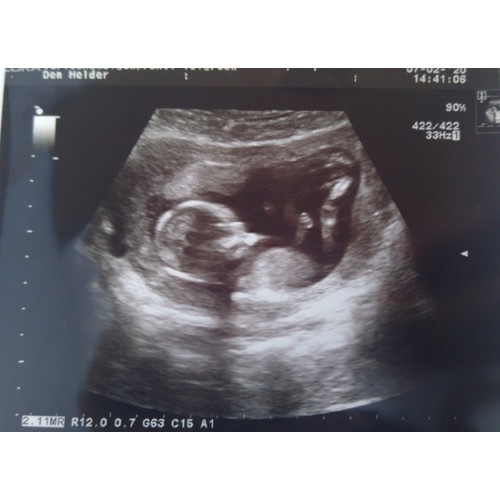

Jongen of een meisje? Wat denken jullie? 😁

Volgens mij zie ik een pipi 💙

Maar je bent zo'n 11w zie ik dus misschien dat het nog zakt. Of niet 😉